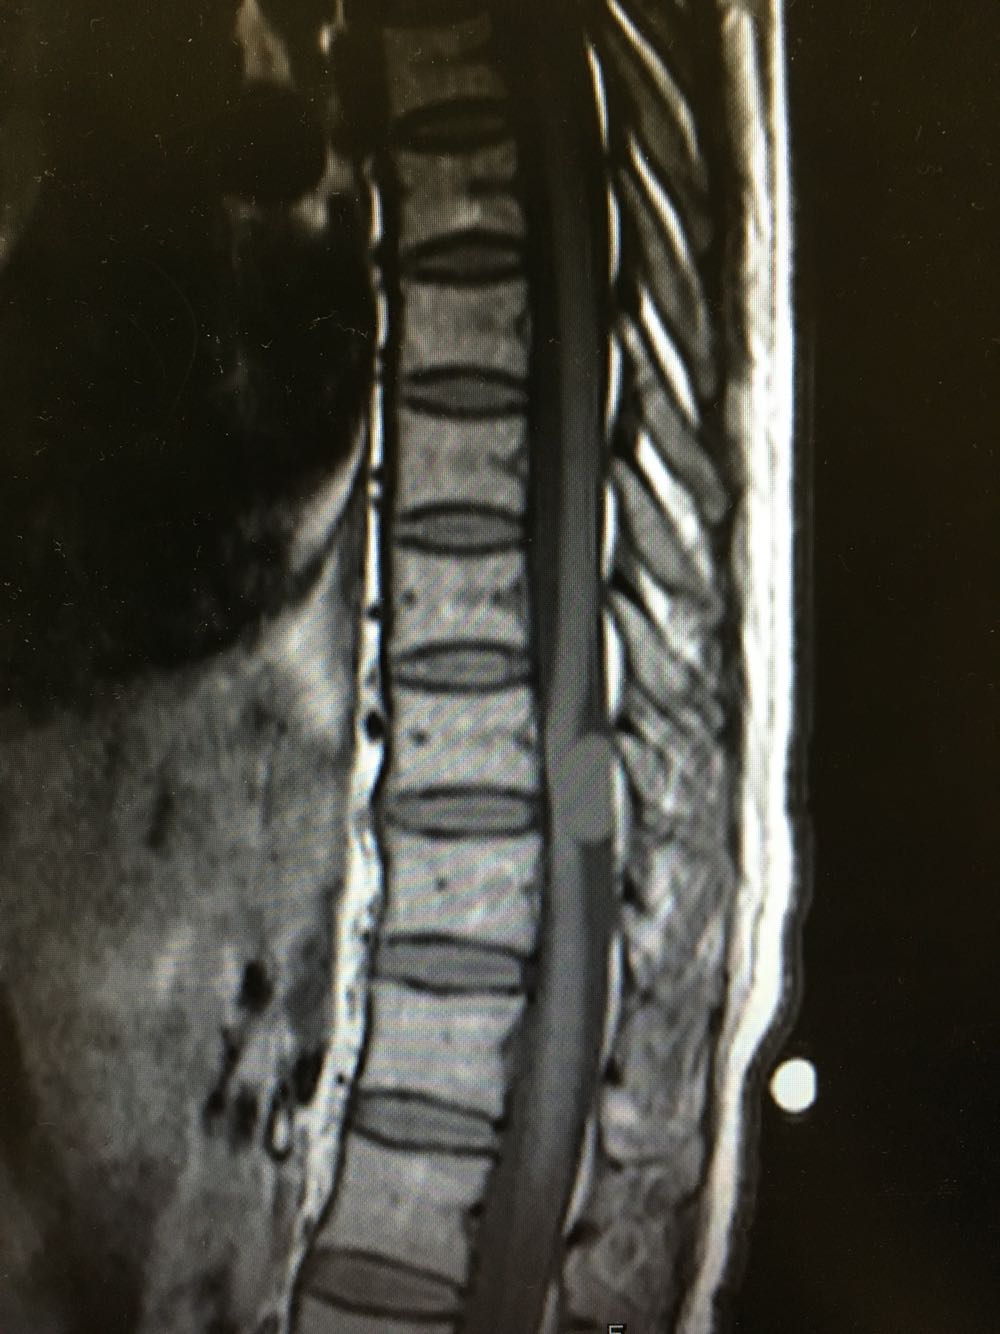

患者,女性,44岁 主诉:进行性双下肢麻木无力1年余 现病史:患者1年前自觉腰痛及脚底脚背麻木不适,至当地医院就诊考虑:腰椎间盘突出,予推拿及针灸治疗,未见明显缓解,症状时有加重,近1周上述症状加重明显,遂至我院就诊,查MR示:T10-11处混杂信号,考虑肿瘤可能,现为进一步诊治收治入院,发病以来,神清,精神可,胃纳夜眠可,二便无殊,体重无明显变化。

查体:左下肢肌力V级,右侧下肢肌力IV级,肌张力正常,膝反射亢进,病理反射未引出,双下肢感觉较差。 辅检:见现病史

诊断:脊髓肿瘤(T10-T11) 治疗:完善术前检查行手术治疗